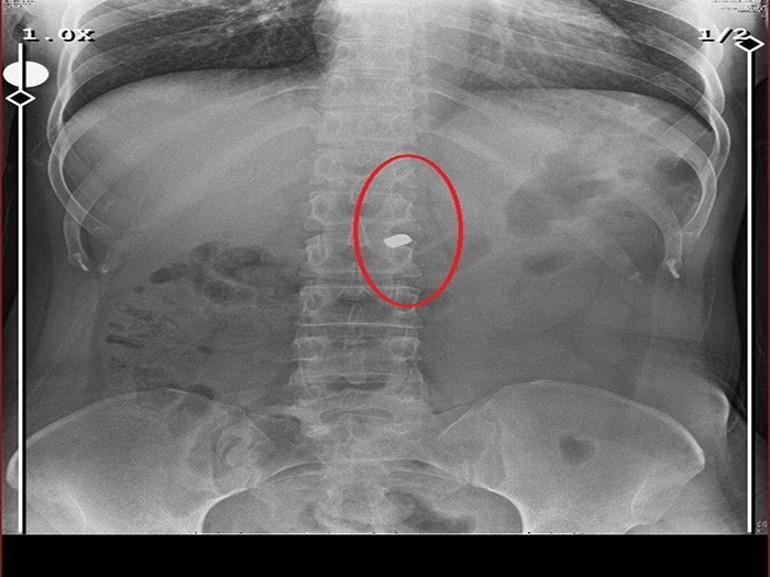

Eski sevgilisi tarafından 8 kurşunla vurularak yaralandığını ancak 2 mermi çekirdeğinin hala vücudunda olduğunu söyleyen Fatma O., hayata tutunmak zorunda olduğunu belirterek, “Hayata tutunmaya çalışıyorum. Bedenimdeki zorluklar ve mermiler yeterince canımı yakıyor, bir de hayat yoruyor. Mendil satarak geçinmeye çalışıyorum. Kimseden bir yardım beklemiyorum ama sadece bir işim olsun istiyorum. Kolum sakat çalışamıyorum. Mendil satıyorum, herkes beni dilenci sanıyor. Ben dilenci değilim. Aşağılamıyorum kimseyi lütfen yanlış anlaşılmasın ama ben bunları hak etmiyorum” dedi.